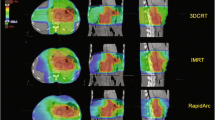

Dynamic IMRT planning (C-IMRT and A-IMRT) was performed with seven noncoplanar fields using 6-MV photon beams for each patient. The isocenter was regarded as the midpoint of the PTVs. Similar gantry angles of 75°, 110°, 145°, 180°, 215°, 250°, and 285° were used in C-IMRT and A-IMRT. All collimator angles in C-IMRT were 0°. In A-IMRT, the collimator angle was 90° for gantry angles of 110°, 180°, 215°, and 285°; it was 0° for gantry angles of 75°, 145°, and 250° (Table 1). Photon dose calculation was performed using the anisotropic analytical algorithm. Heterogeneity corrections were switched on during all dose calculations. The maximum dose rate was set to 300 monitor units (MU)/min. The dose calculation grid was set to 2.5 mm. Because this was a dosimetric study, the gantry angles in both dynamic IMRT plannings were similar to allow comparison of different collimator angles.

VMAT planning was performed with three full arcs using 6-MV photon beams for each patient. The isocenter was regarded as the midpoint of the PTVs. The first arc ran clockwise from 181° to 179° with a collimator angle of 30°, the second arc ran counterclockwise from 179° to 181° with a collimator angle of 330°, and the third arc ran clockwise from 181° to 179° with a collimator angle of 90°. The photon optimizer (version 13.7) algorithm was used to optimize leaf position, dose rate, and gantry speed. Photon dose was calculated using the anisotropic analytical algorithm. Heterogeneity corrections were switched on during all dose calculations. The maximum dose rate was set to 600 MU/min. The dose calculation grid was set to 2.5 mm.

The planning objectives were identical for both dynamic IMRT and VMAT planning. The dose was prescribed to PTV, in accordance with the recommendations of the International Commission on Radiation Units and Measurements 83 report [17]. The prescribed dose was 50.4 Gy in all patients, delivered in daily fractions of 1.8 Gy. The dose was prescribed to cover 95% and 100% of the PTV and CTV, respectively. Care was taken to maintain a difference of < 10% between the prescribed and maximum doses. Axial CT scan slice representations of a patient planned with C-IMRT (A), A-IMRT (B) and VMAT (C) were shown in Fig. 1.